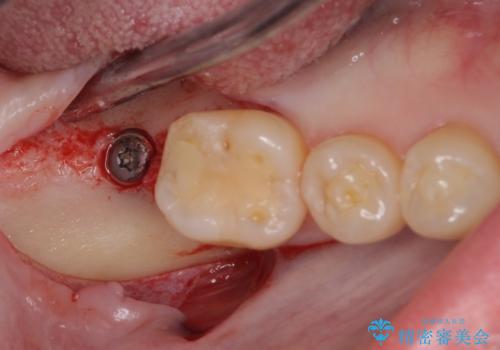

抜歯されたままの奥歯 ストローマンインプラントによる欠損補綴治療

- 抜歯してから放置されている右下の奥歯へのインプラント治療を希望して来院された患者様です。

世界中で高い信頼を得ているストローマンインプラントを用いて治療を行うこととしました。

ストローマン社のSLActiveというインプラントを使用し、インプラント埋入からクラウンが装着されるまで3ヶ月弱という短期間で終えることができました。